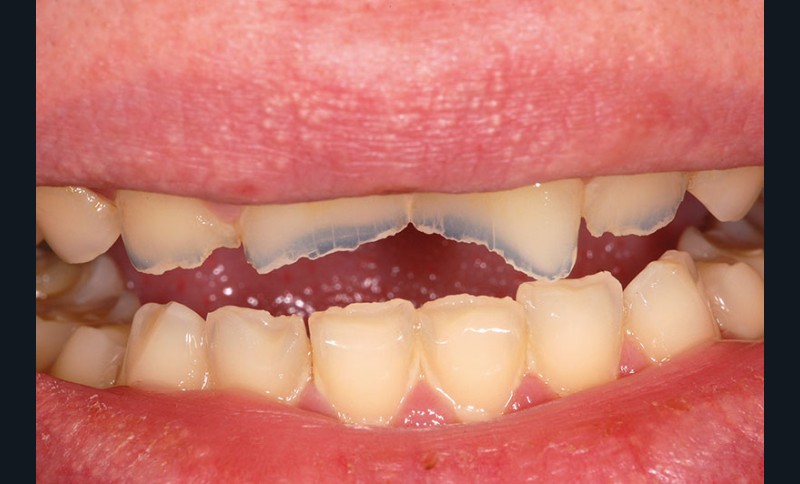

À l’examen clinique, les dents, principalement antérieures, présentent des pertes de substances importantes de classe V selon la classification ACE (Anterior Clinical Erosive Classification) de Vailati [1] (fig. 1 à 6).

Le parodonte marginal est de type 1 selon la classification de Maynard et Wilson [2]. On note également la présence d’une grande quantité de gencive attachée située apicalement par rapport aux lésions dentaires.